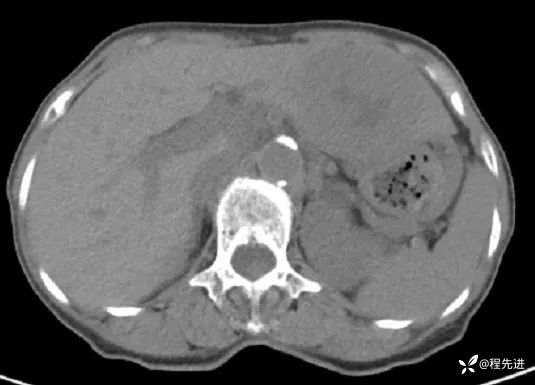

CT平扫: